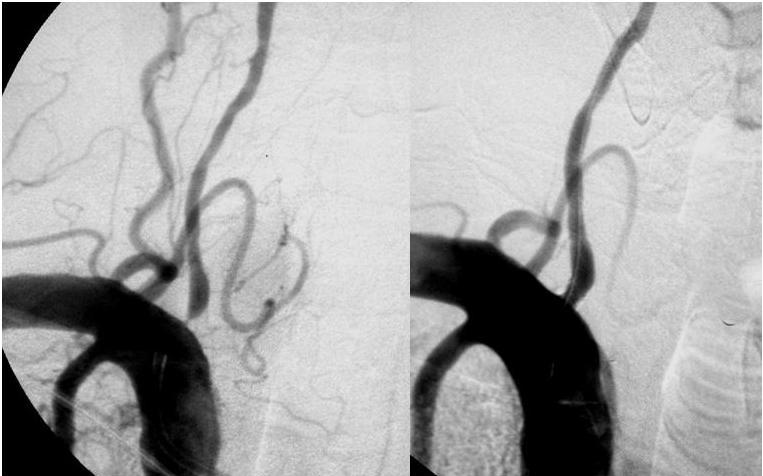

Trombectomía 6 a 24 horas después del accidente cerebrovascular con desajuste entre el déficit y el infarto

N Engl J Med, 18 de noviembre de 2017 Entre los pacientes con accidente cerebrovascular agudo que se sabía que estaban bien 6 a 24 horas antes, y tenían un desajuste entre el déficit clínico y el infarto, los resultados de la discapacidad a los 90 días fueron mejores con la trombectomía además de la atención estándar que con la atención estándar sola.